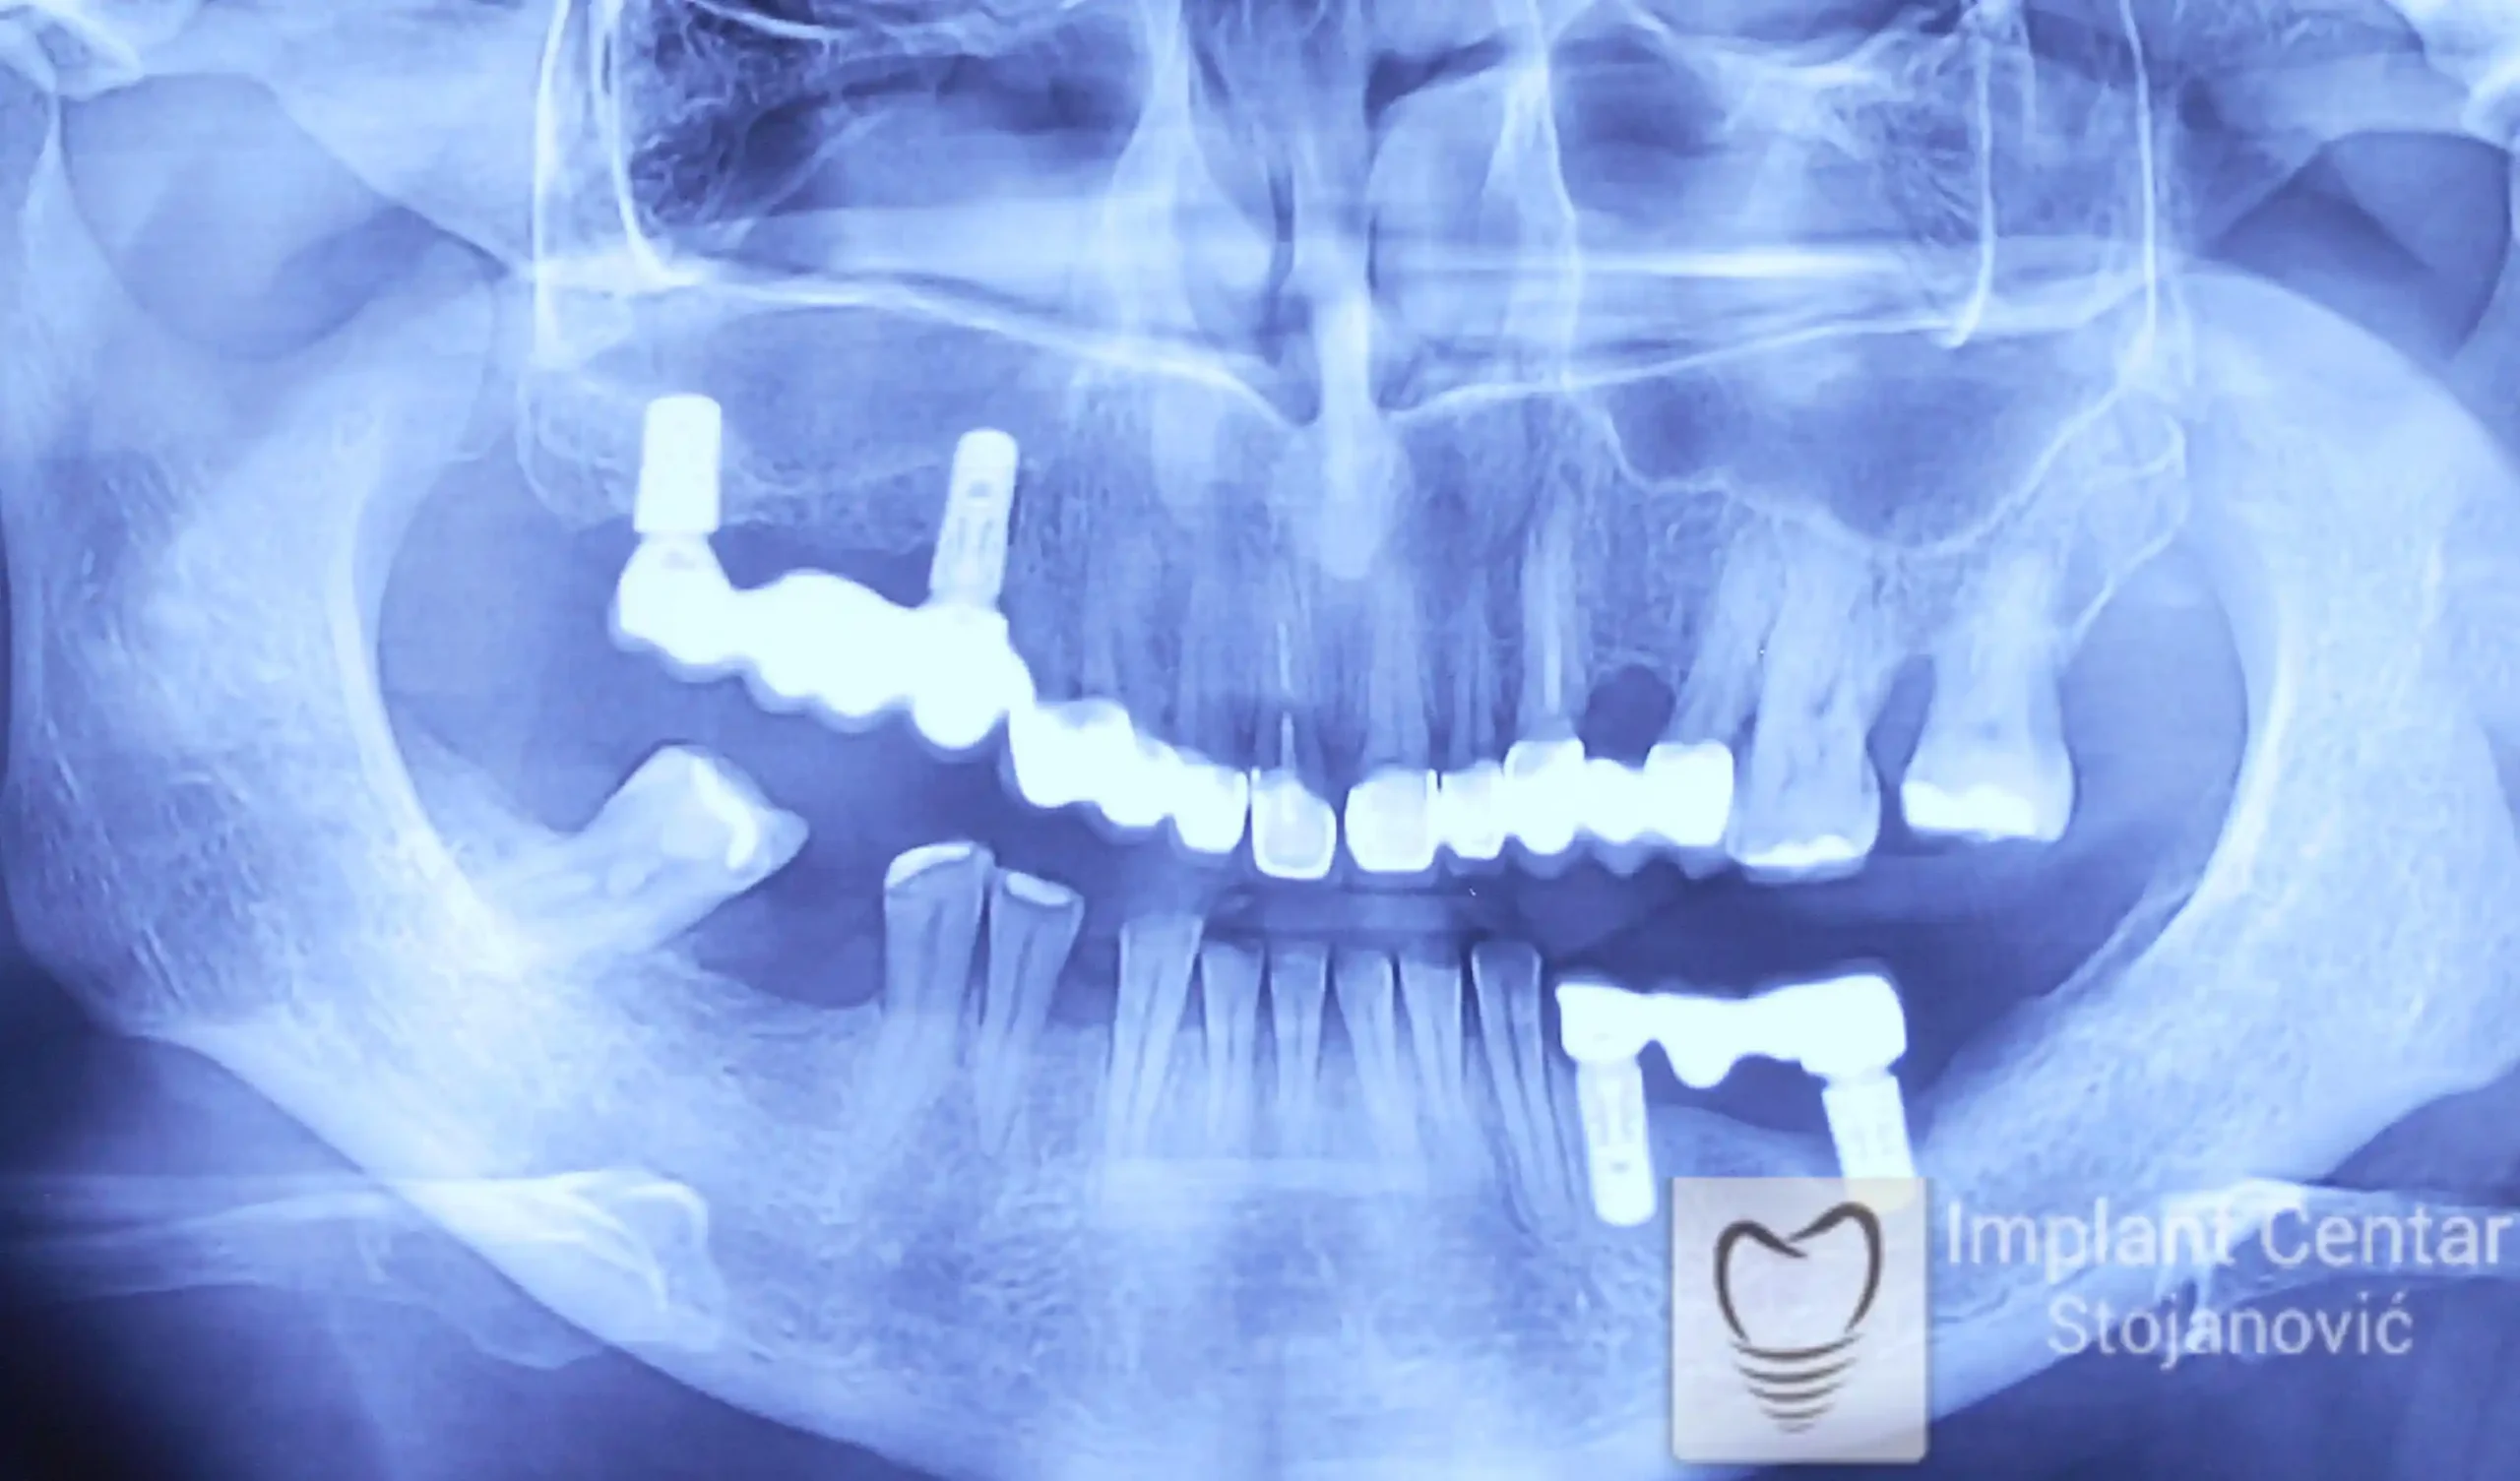

Na slici 1. slici 2. vidi se početno stanje — pacijent je imao prirodne zube, ali samo izradom novih mostova nije bilo moguće postići normalan odnos gornjih i donjih zuba (eugnatan zagrižaj).

Zbog toga je plan terapije uključivao vađenje svih preostalih zuba i ugradnju implantata u gornjoj i donjoj vilici. U gornjoj vilici postavljena su i dva tuberopterigoidna implantata, kao zamena za sinus lift proceduru, što se može videti na ortopan snimku nurađenom odmah nakon ugradnje (slika 3).